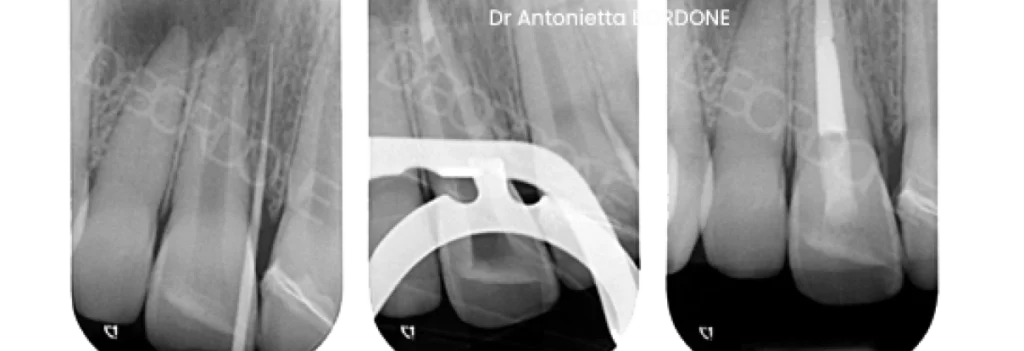

Exemple d’apexification d’une incisive centrale :

Avantages et limites

Cette technique stabilise vite la situation. Elle offre un taux de succès élevé. Cependant, elle n’épaissit pas toujours les parois. La dent peut donc rester plus fragile. D’où l’importance d’une restauration protectrice.